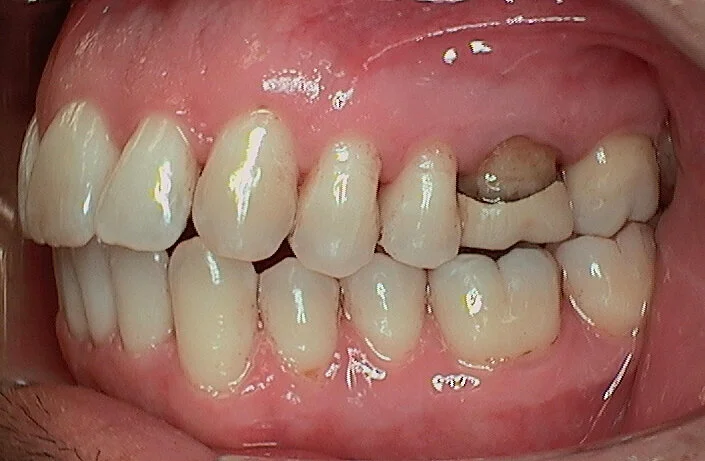

42 y/o male

• Comprehensive Clinical Exam, current Panoramic X-ray and intraoral photos

• Invisalign Comprehensive Treatment

• 2 ClinChecks:

• 1 st ClinCheck : 20 aligners/ 14 day wear

• 2 nd ClinCheck: 8 aligners/ 14 day wear

• (Pt was on 14 day aligner change increments due to his periodontal disease and bone

loss)

• Treatment time: 15 months